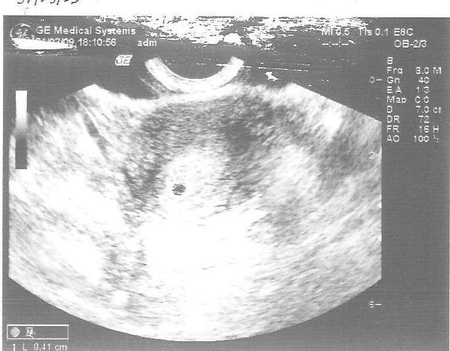

Через 4 дня я повторяла УЗИ(начились проблемы) и там уже всё было видно!!!

И вот первая фотка Даниила(точечка в центре он и есть)):